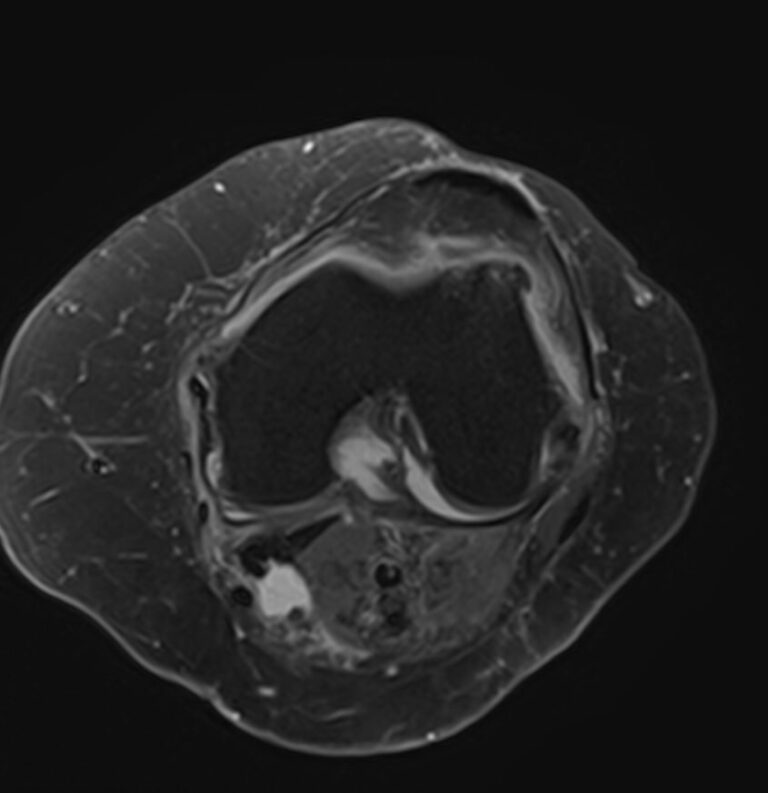

• дегенеративно-дистрофическое поражение коленных суставов (гонартроз);

• воспалительные заболевания коленных суставов (артриты, синовиты);

• врожденные пороки развития коленных суставов (дисплазия, аплазия);

• доброкачественные и злокачественные опухоли коленных суставов и окружающих их тканей.